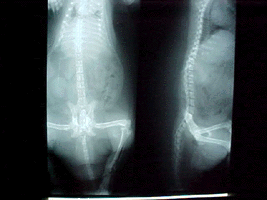

X-ray showing poor bone density X-ray showing improved bone density

Poor Bone Density Good Bone Density

Pelvic X-ray showing poor bone density Pevic X-ray showing good bone density

Malnutrition, poor diet (green bean's, pea's, lettuce); X-rays show very little bone mass or muscle, bones thin and brittle like egg shell, severely deformed legs.

Treatment: Morning: 1/8 tsp. Rep-Cal powder, 1/2 squirt liquid taurine, pinch Echinacea (first three weeks to build up his immune system), 1/3 cup thawed frozen veggies, 10 Cheerios or soy cereal. Lunch: 1/2 cc Pet Tinic (for 4 weeks), 1/8 - 1/4 tsp. colostrum, 1/8 tsp. whey powder, 1 tbsp. skunk mixture, sardines, or salmon; 1 tsp. low fat yogurt. 3:00 PM: Vitamin K, fresh vegetables, 1/8 tsp. Vitamin C, tofu or raw oats. Supper: 1/8 tsp. Rep-Cal., dab of Feliobite II, 1/8 tsp. whey powder, fresh veggies, chicken or Skunk mixture, 1 tsp. low fat yogurt, blueberry, apple or pear (small amount). Nighttime snack: four small pieces of Bil-Jack dog food. Used Reptile Light [UV+ lamp] for 15 minutes per day while eating. X-rays in 58 days show remarkable regrowth in bones. Still badly deformed. Added 1/4 tsp. Synovi-MSM and B-complex to diet twice daily, dropped the whey to 1/8 tsp. daily.